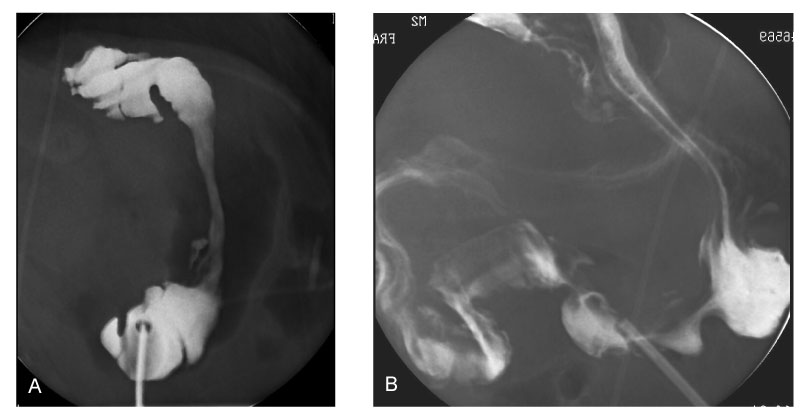

Fig. 2

Upper GI series at 14th day of surgery shows poor peristaltic activity of the stomach and delayed passage of barium through the pylorus. B. Upper GI series at 26th day of surgery reveals propulsive peristaltic activity of the antrum with prompt passage of barium through the pylorus to the duodenum immediately on injection of erythromycin.

Fig. 2 Upper GI series at 14th day of surgery shows poor peristaltic activity of the stomach and delayed passage of barium through the pylorus. B. Upper GI series at 26th day of surgery reveals propulsive peristaltic activity of the antrum with prompt passage of barium through the pylorus to the duodenum immediately on injection of erythromycin.